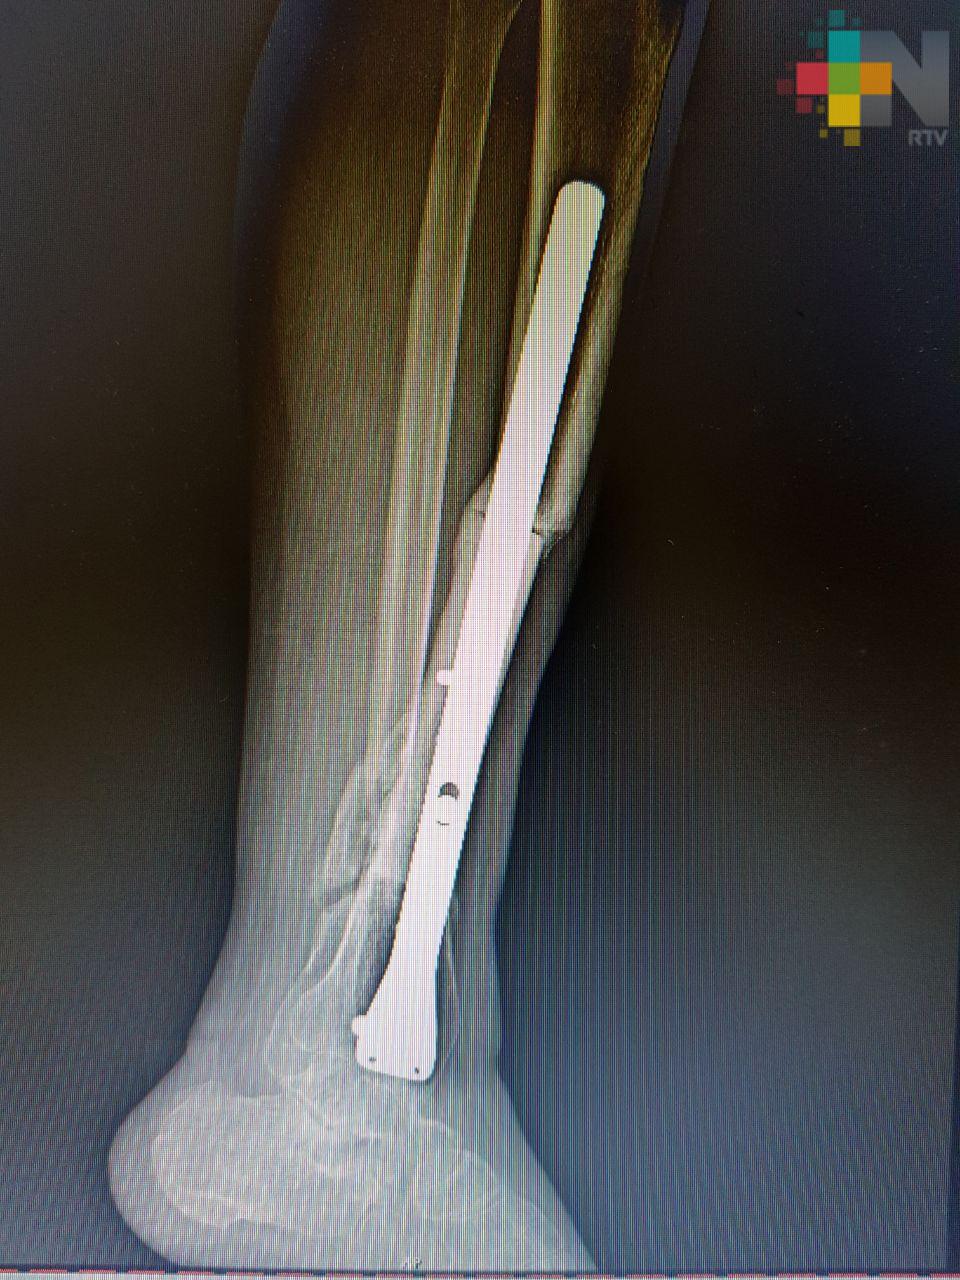

Xalapa, Ver.- Un equipo médico multidisciplinario del Instituto Mexicano del Seguro Social (IMSS) en Veracruz restituyó 11 centímetros de hueso de la pierna de un hombre que sufrió un accidente, mediante el trasplante de tejido óseo cadavérico que le permitió conservar la extremidad y volver a caminar.

El hueso implantado se obtuvo del Banco de Tejidos en el Estado de México a solicitud expresa de los médicos tratantes. El injerto fue realizado en el Hospital General de Zona No. 11 «Ignacio García Téllez», de la ciudad de Xalapa.

Luis René transitaba en su motocicleta cuando fue arrollado por un vehículo y, como resultado del accidente, perdió una tercera parte de la tibia y el peroné de la extremidad izquierda.

Fue aproximadamente una pérdida de 11 centímetros de hueso, por lo que al llegar al hospital se le realizaron cirugías para preservar la viabilidad de los tejidos afectados y la colocación de placas en las partes óseas.

Por la fractura expuesta, la fragmentación de los huesos y debido a que la pierna estaba unida al tobillo sólo por tejido blando, un procedimiento inmediato era la amputación, explicó el especialista en Traumatología y Ortopedia del Hospital General de Zona No. 11, Eduardo Morales Martínez, quien encabezó al equipo multidisciplinario que atendió a Luis René.

Sin embargo, se buscó la forma de salvar el miembro y mediante la recuperación de la viabilidad de los tejidos blandos se optó por el implante óseo. El doctor Morales explicó que en este caso se activó el protocolo para solicitar tejido óseo y al cabo de algunos meses se logró obtener el hueso de un cadáver apto para implantarse.

Fue necesario recurrir a un implante de hueso porque era una lesión muy extensa. No había sustento, no había hueso, no había de dónde fijar la placa. Era prácticamente una pérdida total, el pie estaba suelto y no había soporte que uniera esas dos estructuras, explicó el especialista. El riesgo de pérdida de la extremidad fue alto y el proceso de recuperación fue de aproximadamente un año.

Detalló que actualmente Luis está totalmente recuperado, es capaz de caminar sin asistencia, puede apoyarse sin soporte, es independiente para todas sus actividades y lo más importante, es que preservó su pierna.

La recuperación del hueso está al 100, ya tiene una integración radiográfica del injerto y debe continuar con el ejercicio de deambulación, puntualizó.